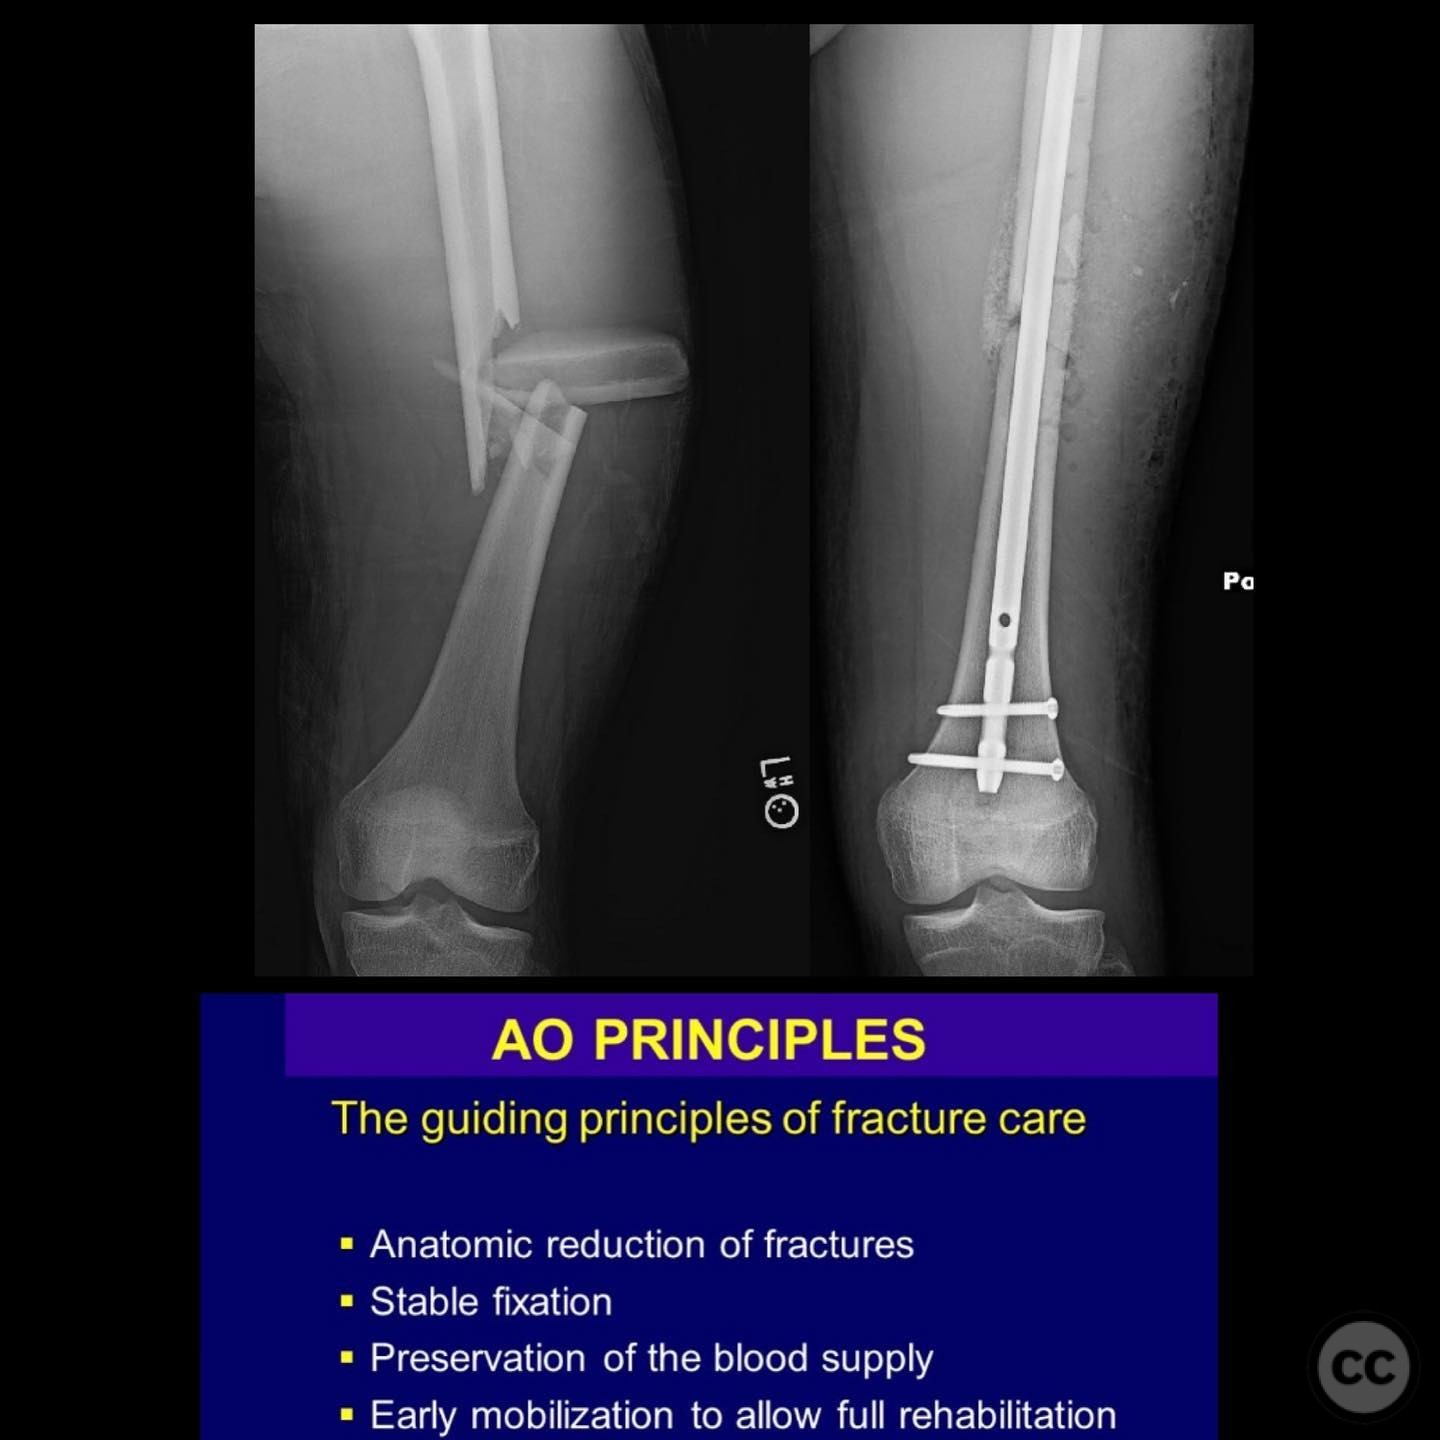

Comminuted Diaphyseal Femur Fracture in a 16-Year-Old

Clinical and radiological findings:  A 16-year-old male sustained a comminuted diaphyseal femur fracture after a 50-foot fall while rock climbing. The patient presented with multiple injuries but was well resuscitated and cleared for surgical treatment of the femur fracture within 24 hours. The injury was closed, with no neurological or vascular compromise noted.

Preoperative Plan

Planning remarks:  The preoperative plan involved an open reduction and internal fixation (ORIF) due to the complexity of the fracture and the presence of a large incomplete napkin ring segment that could not be managed with closed nailing techniques. The anatomical approach was planned through a lateral incision to allow direct access to the fracture site for reduction and fixation.

Orthopaedic implants used:   Intramedullary nail, autologous bone graft from reamings.